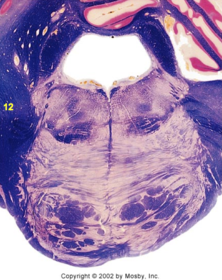

| Nucleus gracilis | |

| Accessory nucleus | |

| Medial longitudinal faciculus | |

| Pyramidal decussation | |

| Medullary pyramids | |

| Anterior spinocerebellar tract | |

| ALS | |

| Posterior spinocerebellar tract | |

| Spinal tract of V | |

| Spinal nucleus of V | |

| Nucleus cuneatus | |

| Fasciculus cuneatus | |

| Fasciculus gracilis | |

| Central canal | |

| Internal acruate fibers | |

| Lateral (external/accessory) cuneate nucleus | |